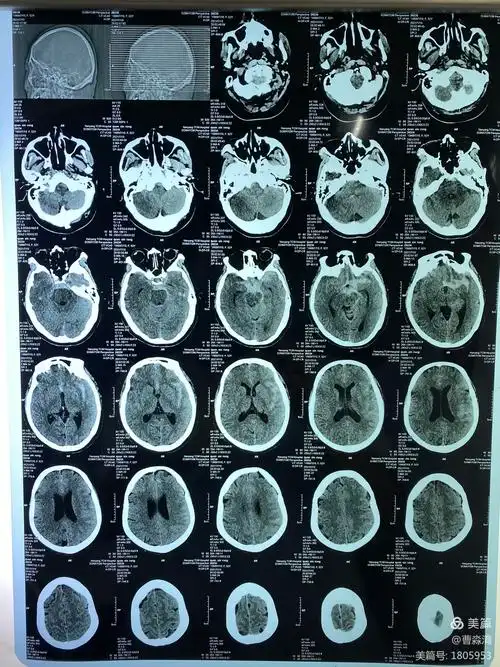

扁头 br>翻出了去年拍的头部ct br>当时拿到片子第一时间跟闺蜜吐槽

因突发头痛3小时入院,发病2小时我院急诊头ct

南阳市中医院脑外科为颅内动脉瘤破裂合并出血患者生命

请教ct大神一张头部ct

颅骨缺如修复前头颅ct片子